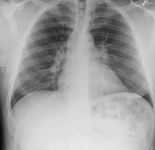

Radiografía de tórax que muestra fibrosis intersticial en un paciente con toxicidad pulmonar por amiodarona

De la colección personal del Dr. A. Pataka y el Profesor P. Argyropoulou, Aristotle University, Thessaloniki, Grecia; usado con autorización